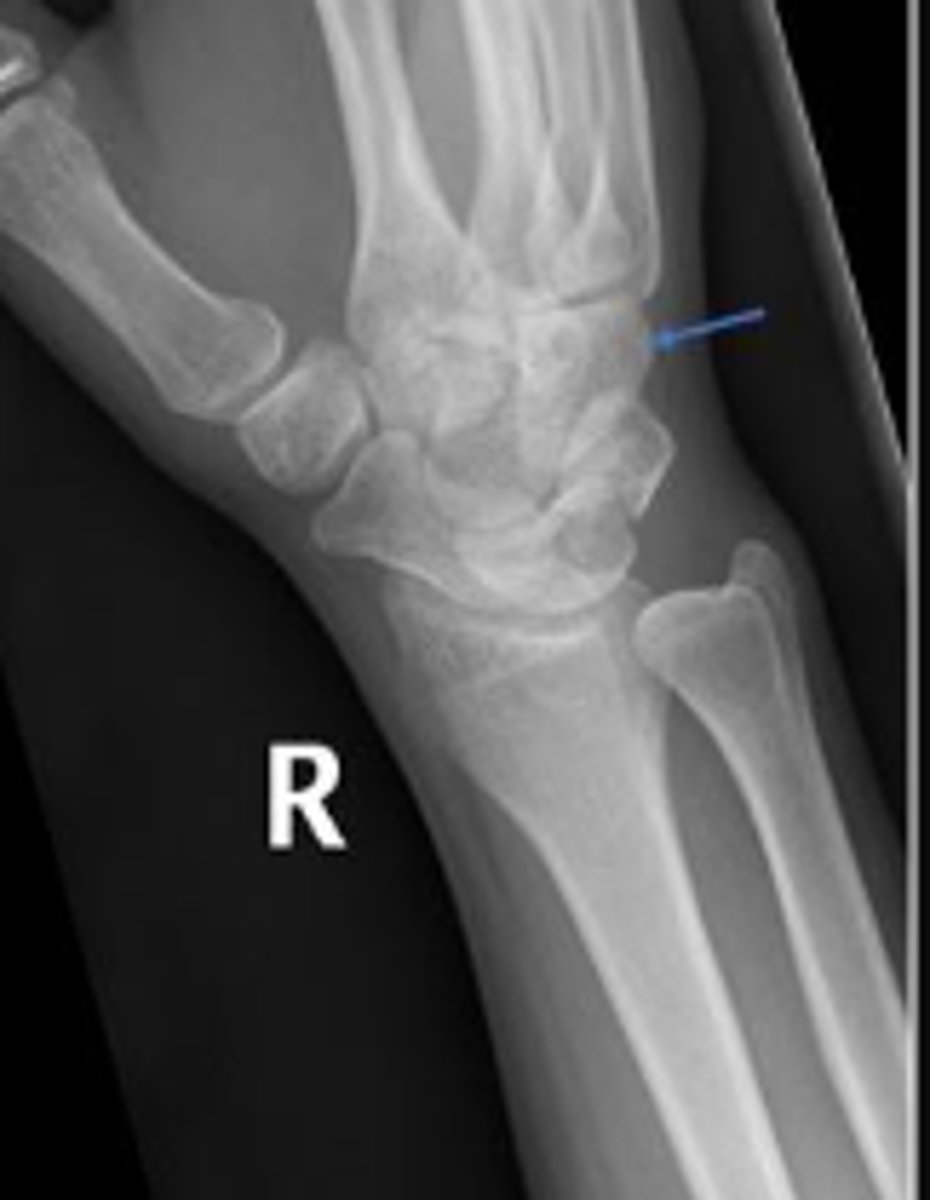

Right scaphoid

What is the arrow pointing to?

DRUJ

< and equal to 2mm

What is the normal measurement of this space?